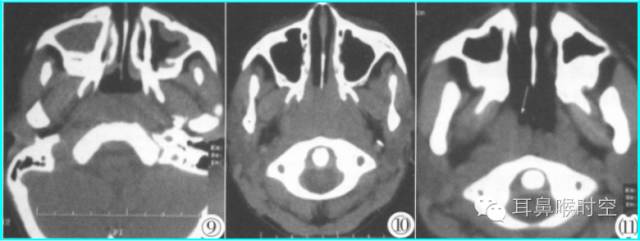

儿童腺样体肥大依据CT 表现分为3 型:

CT表现:

为鼻咽顶后壁增厚,形成肿块

前缘平直或略凹陷,堵塞后鼻孔

鼻咽腔变形、狭窄,上气道变窄。

CT 表现:

除Ⅰ型外

同时有上颌窦、筛窦黏膜增厚,窦腔变窄等慢性鼻窦炎表现及鼻甲肥大和/或鼻中隔偏曲

除Ⅰ型的CT表现外

还有咽鼓管咽口粘连狭窄及中耳乳突积液,即分泌性中耳炎表现。

标准CT 轴位像:

鼻咽气腔均不同程度变形变窄(图7,8) , 不规则形,横条形,完全闭塞。

增大的腺样体呈软组织密度,均匀一致,与头长肌相近,呈弥漫性肿块形(图9)、嵌入鼻后孔肿块形(图10)、单侧肿块形(图11)。

静脉增强扫描呈轻-中度强化。

鼻咽气腔形态

腺样体形态

弥漫性肿块形(图9) 嵌入鼻后孔肿块形(图10) 单侧肿块形(图11)